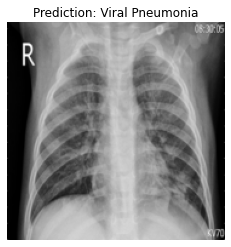

Currently, there is an urgent need for efficient tools to assess the diagnosis of COVID-19 patients. In this project, we propose a constructive solution for detecting and labeling infected tissues on CT lung images of such patients. To cut down false positives our model is trained on 4 types of lung CT images : COVID, Viral Pneumonia, Lung Opacity and normal images to get the best possible results with highest accuracy.

We built it using Tensorflow 2.x using Python. We have developed a Convolutional Neural Network model with an average accuracy of more than 85%. We built the WebApp using Streamlit library for easy interaction with the prediction model.

We are proud that among the top 5 models, one of our models achieved 88.8% accuracy with very low loss.